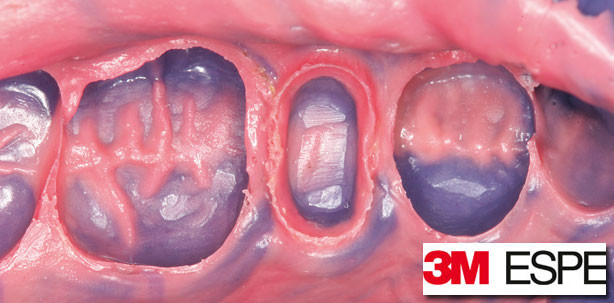

Foto: © 3M ESPE

Mit dem ursprünglichen, seit 1965 verfügbaren Polyether hat das gesamte Impregum-Portfolio von 3M ESPE verschiedene Eigenschaften gemeinsam. Dazu zählen eine hohe Zeichnungsschärfe, die dem exakten Anfließverhalten durch die natürliche Hydrophilie des Materials zu verdanken ist, sowie die dimensionsgetreue Wiedergabe. Letztere wird sichergestellt, da Polyether additionsvernetzend sind und nahezu keine Schrumpfung aufweisen. Hinzu kommen eine hohe Standfestigkeit, ein exaktes Abbindeverhalten und ein gutes Rückstellvermögen.